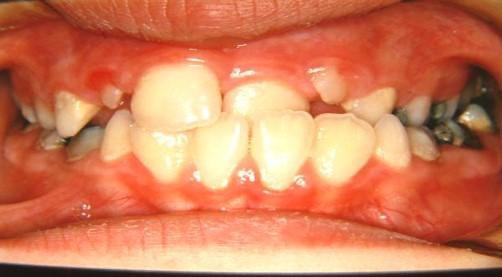

Γ6. Διόρθωση οδοντοσκελετικών προβλημάτων πριν την αλλαγή των μόνιμων δοντιών

- Προγναθισμόs άνω γνάθου - Προγναθισμόs κάτω γνάθου - Σταυροειδής σύγκλεισηΠροσωπική ασυμμετρία

- Προγναθισμόs άνω γνάθου

1η περίπτωση

Αρχική οδοντοσκελετική κατάσταση παιδιού με προγναθισμό άνω γνάθου και έντονη οριζόντια πρόταξη άνω τομέων Η σημασία της στοματικής υγιεινής και ορθοδοντικής

026

πρόληψης

027 Αμέσως μετά το τέλος της ορθοδοντικής θεραπείας. Οι αλλαγές στην οδοντική του σύγκλειση αλλά και στο πρόσωπο είναι εμφανείς 15 χρόνια μετά την αρχική περάτωση της θεραπείας, το αποτέλεσμα παραμένει σταθερό και ο ασθενής απέκτησε ένα υγιές και αρμονικό χαμόγελο και πρόσωπο. Η σημασία της στοματικής υγιεινής και ορθοδοντικής πρόληψης

028 Δεύτερη περίπτωση Αρχική κατάσταση Η σημασία της στοματικής υγιεινής και ορθοδοντικής πρόληψης